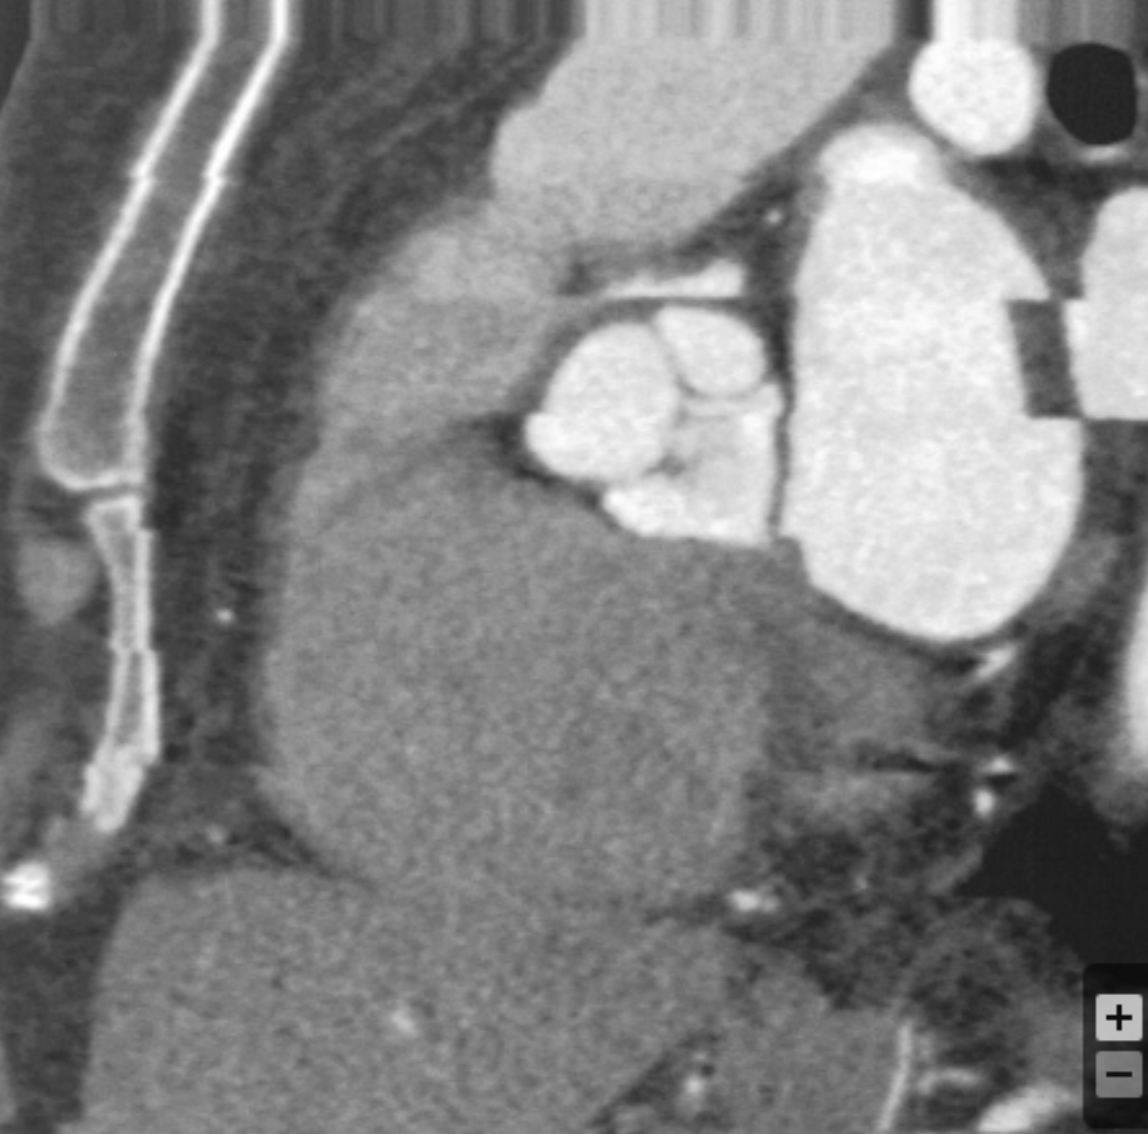

Describe the findings and diagnosis:

LV apical thrombus